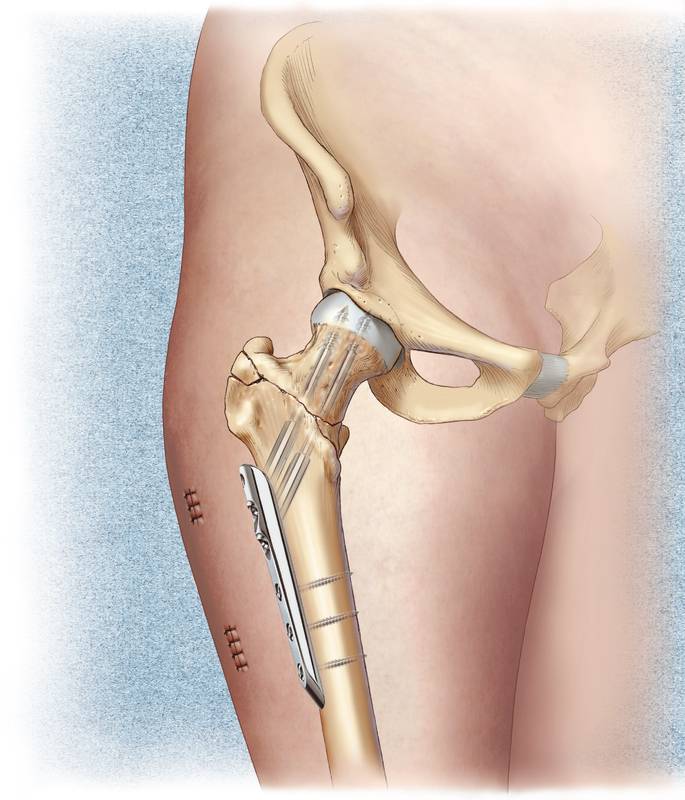

- при доброкачественных новообразованиях выполняют резекцию пораженного участка в сочетании с остеосинтезом (скреплением отломков). Если возник большой дефект тканей – проводят замещение алло- или гомотрансплантатом в сочетании с остеосинтезом;

- при поражении сустава или околосуставной области проводят эндопротезирование – замену сустава на искусственный;

- если диагностировано нарушение целостности диафиза, то поврежденный участок укрепляют костным цементом или замещают дефект трансплантатом.

Костные фрагменты фиксируют с помощью гвоздей, пластин, штифтов, винтов или аппарата Илизарова.